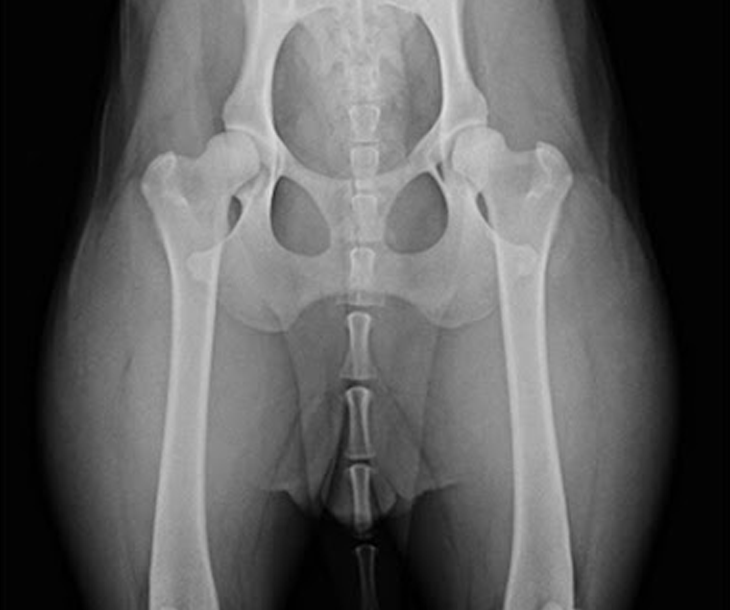

고관절 이형성증

강아지 고관절이형성증은 주로 비정상적인 관절 구조와 정상적인 지탱을 위한 근육,연결 조직,인대의 느슨함과 관련이 있습니다.이 질병은 70%가 유전적 요인과 관련이 있으며,후천적인 경우에는 관절 불안정성이나 환경적 요인에 의해 발생할 수 있습니다.